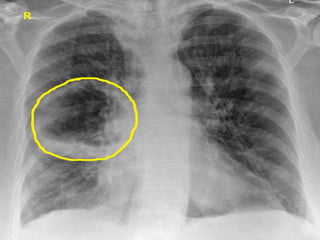

Investigation

• Blood – normocytic anemia

• Chest X ray – the wall of abscess cavity

completely surrounds the radiolucent area

• CT scan of thorax shows lung abscess

• Bronchoscopy – to exclude malignancy, to